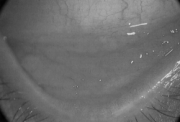

Akute Bindehautentzündungen durch Bakterien oder Pilze sind heute relativ selten geworden. Ihre Bekämpfung gelingt meist mit Breitband-Antibiotika. Bei der weniger rasch bis chronisch verlaufenden Infektion mit Chlamydien - das sind sehr kleine, sich nur innerhalb lebender Zellen vermehrenden Bakterien , die sich nicht nur in der Bindehaut sondern in allen Schleimhäuten aufhalten - muß nicht nur der Erkrankte, sondern auch sein Partner, zu dem er intime Kontakte pflegt, mitbehandelt werden, damit die Infektionskette unterbrochen wird. Die Therapie ist konsequent und über mindestens 3 Wochen durchzuführen, denn nur unter dieser Voraussetzung kann die chronische Bindehautentzündung mit den Riesenfollikeln (Ansammlung von weißen Blutkörperchen) abheilen. Das ist auch deshalb wichtig, weil bei Verschleppen dieser Erkrankung Dauerschäden der Hornhaut und der Innenseite des Oberlids drohen.

Chlamydien-Konjunktivitis